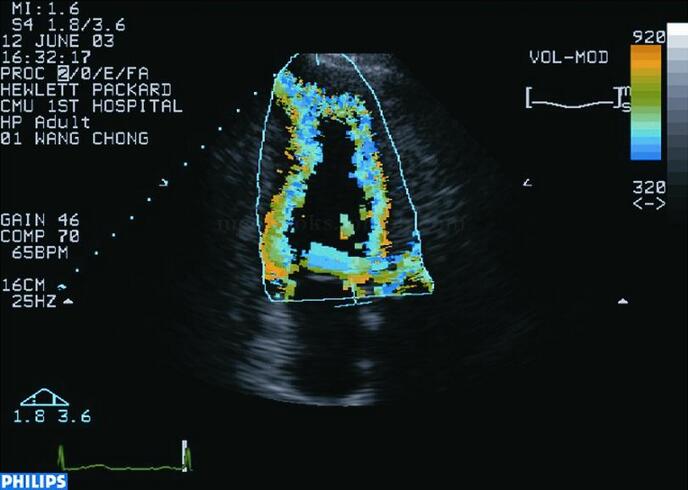

彩色室壁运动技术自动实时识别和跟踪血液与组织界面,以彩色梯度表示(图2‐1‐152,图2‐1‐153),其优点是直观、快速,缺点是受二维图像质量和人为操作误差的影响较大。

图2‐1‐152 正常人心尖两腔心切面彩色室壁运动技术(CK)舒张期显像

图2‐1‐153 正常人心尖两腔心切面CK技术收缩期显像